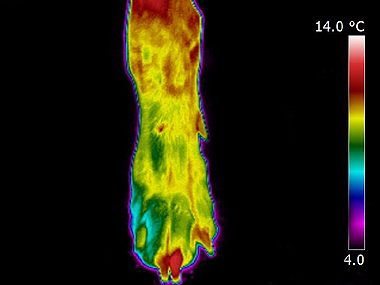

Veterinary Thermal Imaging Offers New Services For Pets Barn In